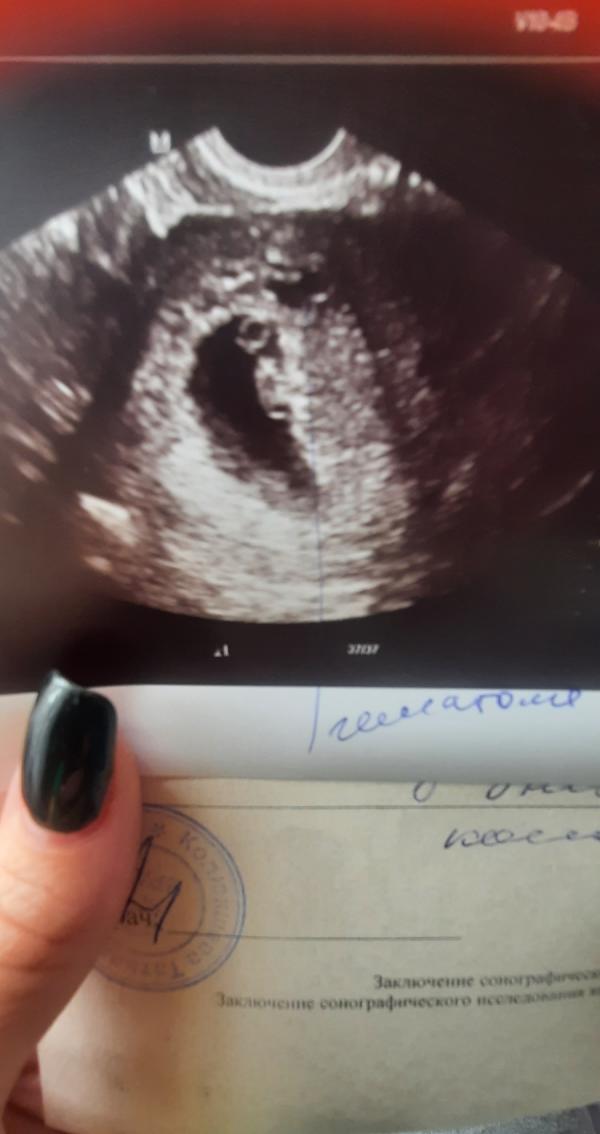

Вот и я прошла сегодня первое УЗИ))) сердечко бьётся, поставили срок 6,5 недель. Есть маленькая гематомка, надеюсь что всё будет хорошо 🙏